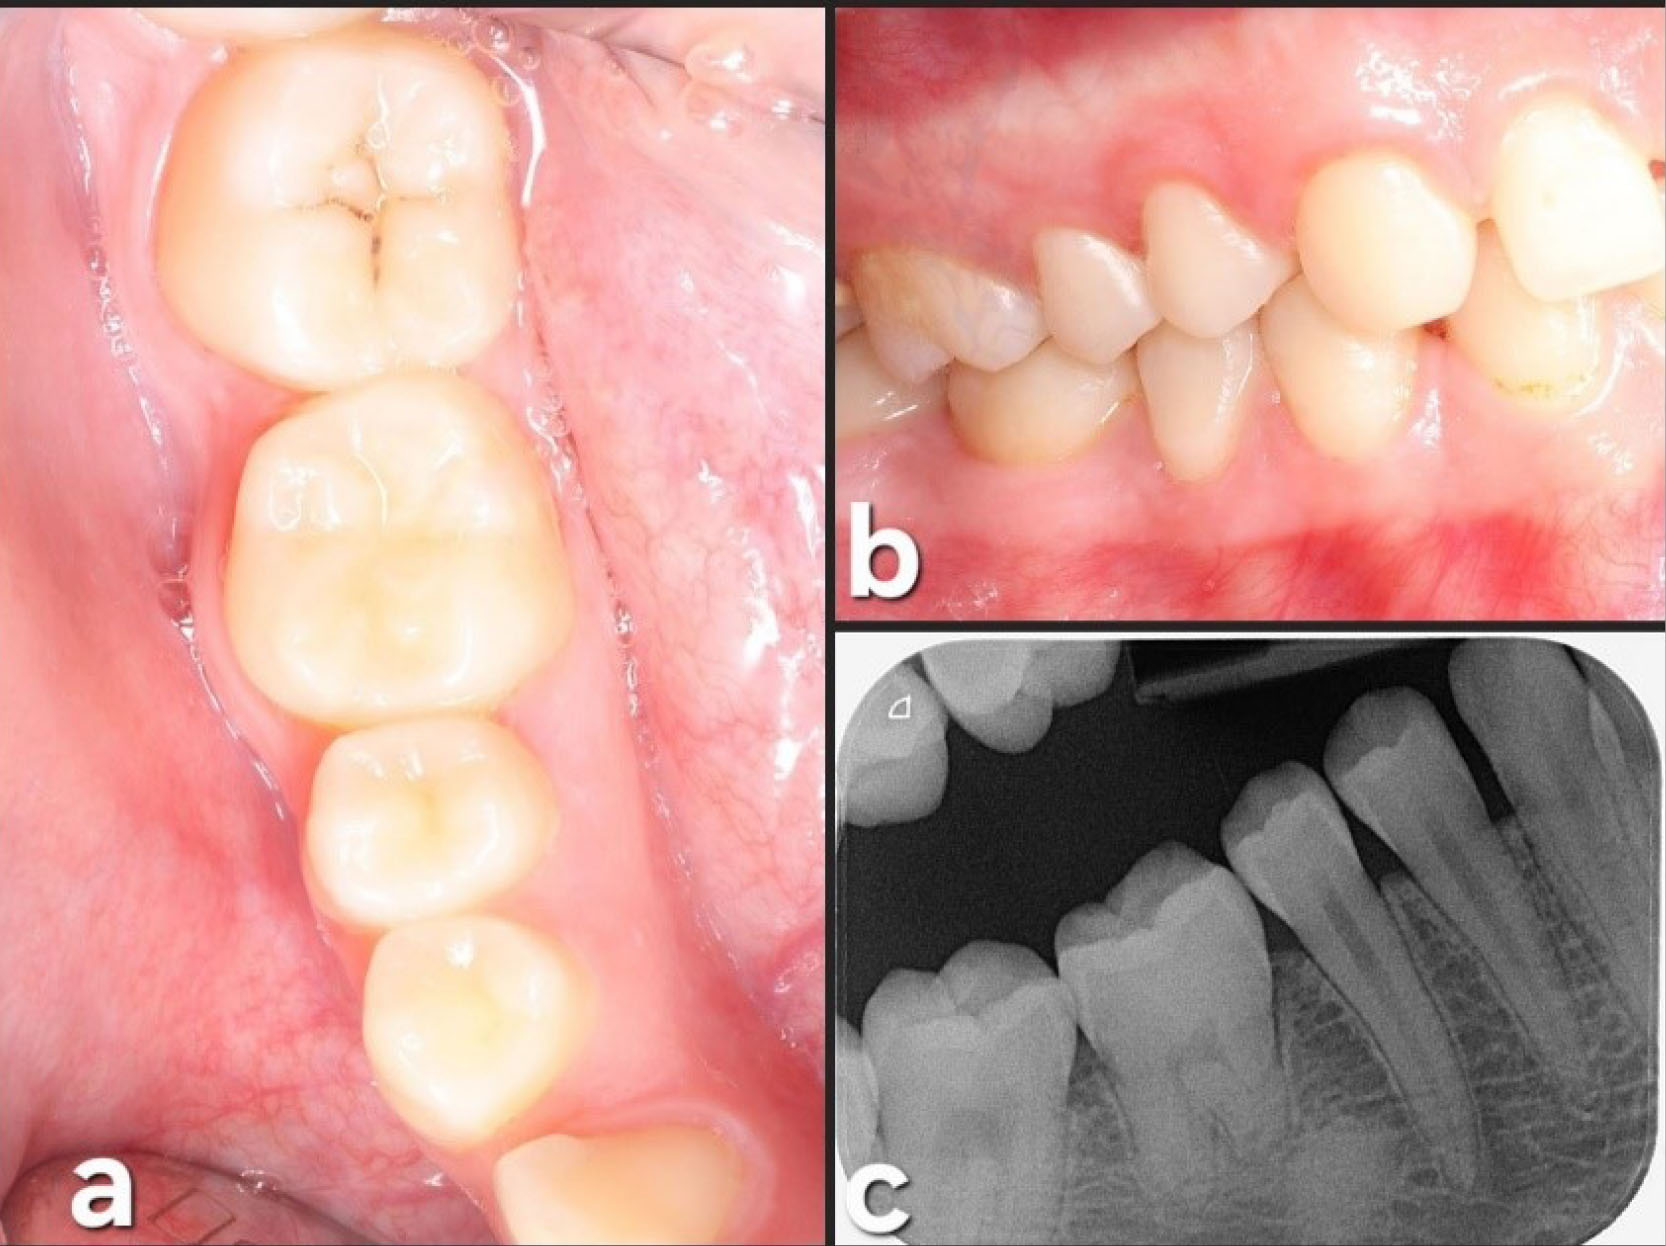

Upon intraoral examination, inflammation was observed on the buccal side of tooth #4.6 (lower right first molar), accompanied by pain upon pressure and the presence of purulent drainage. Bleeding on probing was also registered, and a pocket depth of 6 mm on the buccal side of the affected tooth was observed (Figure 1). The Endodontics Department established a provisional diagnosis of vertical root fracture with furcal involvement and infection, recommending dental extraction as the preferred treatment. The DAT option was introduced after thorough discussions with the patient and her parents. This alternative was considered since both teeth (left lower third molar and right lower first molar) needed extraction. Considering the patient’s age, dental implant placement was deemed contraindicated. A cone-beam computed tomographic (CBCT) scan was subsequently requested to evaluate the case further.

Figure 1.

Diagnosis and planning. (a and b) Preoperative intraoral pictures; occlusal and lateral views. (c) Panoramic view before endodontic treatment. (d and e) Periapical radiographs during endodontic treatment. (f) New periapical radiograph before autotransplantation